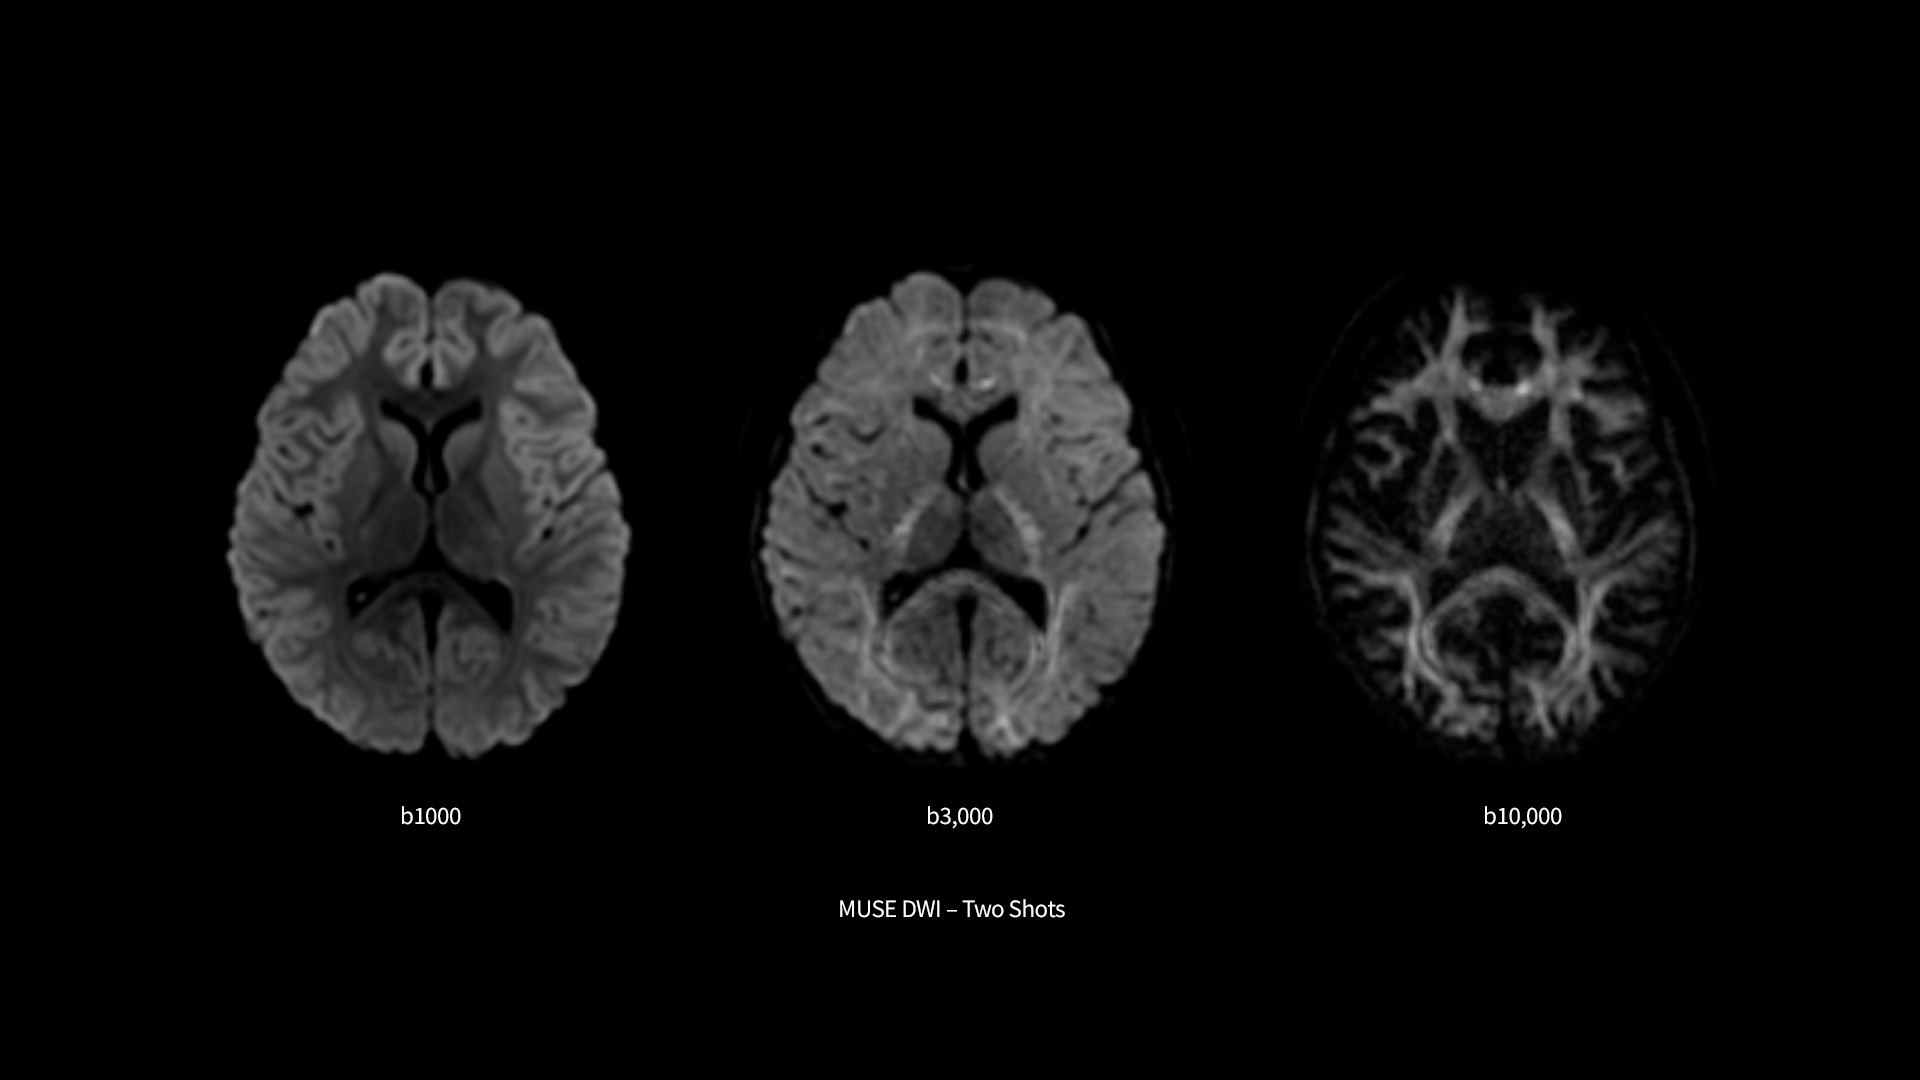

​SIGNA™ Premier supports the most demanding applications, such as Connectome-type studies that require Ultra-short TE diffusion imaging and high-resolution resting state fMRI. While it is a pioneering MRI system for cutting-edge research, it offers all the features needed to deliver routine clinical throughput. This includes delivering high end diagnostic image quality while ensuring the highest level of patient comfort.​

A powerful science tool with remarkable versatility

SIGNA™ Premier exemplifies many powerful robust attributes that makes it an exceptional MR for academic institutions. Alongside the SuperG gradients, which are proficient in executing the Human Connectome Protocol (HCP), the system has impeccable fMRI stability, a high RF-channel count with AIR™ Coils and a suite of deep learning applications.